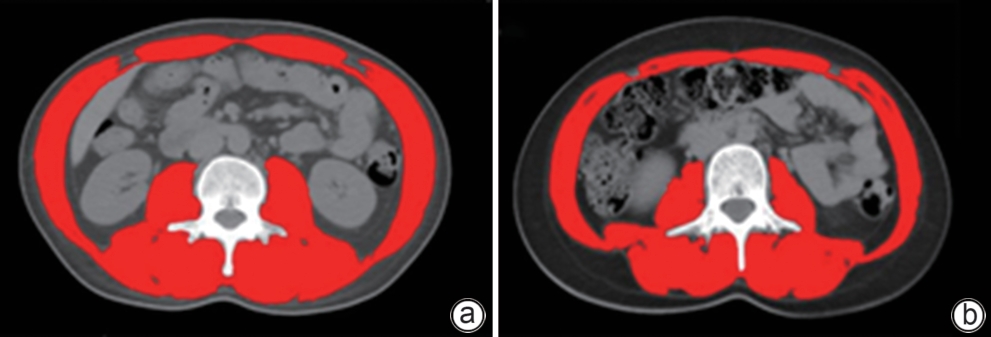

Establishment and validation of a risk prediction model for 90-day mortality in patients with acute-on-chronic liver failure based on sarcopenia

Huina CHEN, Ming KONG, Siqi ZHANG, Manman XU, Yu CHEN, Zhongping DUAN

2025, 41(6): 1135-1142. DOI: 10.12449/JCH250620

Abstract(1017) HTML (295) PDF (2616KB)(61)

Abstract:

Objective  To establish and validate a new prediction model for the risk of death in patients with acute-on-chronic liver failure (ACLF) based on sarcopenia and other clinical indicators, and to improve the accuracy of prognostic assessment for ACLF patients.  Methods  A total of 380 patients with ACLF who were admitted to Beijing YouAn Hospital, Capital Medical University, from January 2019 to January 2022 were enrolled, and they were divided into training group with 228 patients and testing group with 152 patients in a ratio of 6∶4 using the stratified random sampling method. For the training group, CT images were used to measure the cross-sectional area of the skeletal muscle at the third lumbar vertebra (L3), and L3 skeletal muscle index (L3-SMI) was calculated. Sarcopenia was diagnosed based on the previously established L3-SMI reference values for healthy adults in northern China. Univariate and multivariable Cox regression analyses were used to establish a sarcopenia-ACLF model which integrated sarcopenia and clinical risk factors, and a nomogram was developed for presentation. The area under the ROC curve (AUC) was used to assess the predictive performance of the model, the calibration curve was used to assess the degree of calibration, and a decision curve analysis was used to investigate the clinical application value of the model. The independent-samples t test or the Mann-Whitney U test was used for comparison of continuous data between two groups, and the chi-square test was used for comparison of categorical data between two groups. The Kaplan-Meier method was used to plot survival curves, and the Log-rank test was used for comparison between groups. The DeLong test was used for comparison of AUC between different models.  Results  The multivariate Cox regression analysis showed that sarcopenia (hazard ratio [HR]=1.962, 95% confidence interval [CI]: 1.185‍ ‍—‍ ‍3.250, P=0.009), total bilirubin (HR=1.003, 95%CI: 1.002‍ ‍—‍ ‍1.005, P<0.001), international normalized ratio (HR=1.997, 95%CI: 1.674‍ ‍—‍ ‍2.382, P<0.001), and lactic acid (HR=1.382, 95%CI: 1.170‍ ‍—‍ ‍1.632, P<0.001) were included in the sarcopenia-ACLF model. In the training cohort, the sarcopenia-ACLF model had a larger AUC than MELD-Na score in predicting 90-day mortality in patients with ACLF (0.80 vs 0.73, Z=1.97, P=0.049). In the test cohort, the sarcopenia-ACLF model had a significantly larger AUC than MELD score (0.79 vs 0.69, Z=2.70, P=0.007) and MELD-Na score (0.79 vs 0.68, Z=2.92, P=0.004). The calibration curve showed that the model had good calibration ability, with a relatively good consistency between the predicted risk of mortality and the observed results. The DCA results showed that within a reasonable range of threshold probabilities, the sarcopenia-ACLF model showed a greater net benefit than MELD and MELD-Na scores in both the training cohort and the test cohort.  Conclusion  The sarcopenia-ACLF model developed in this study provides a more accurate tool for predicting the risk of 90-day mortality in ACLF patients, which provides support for clinical decision-making and helps to optimize treatment strategies.